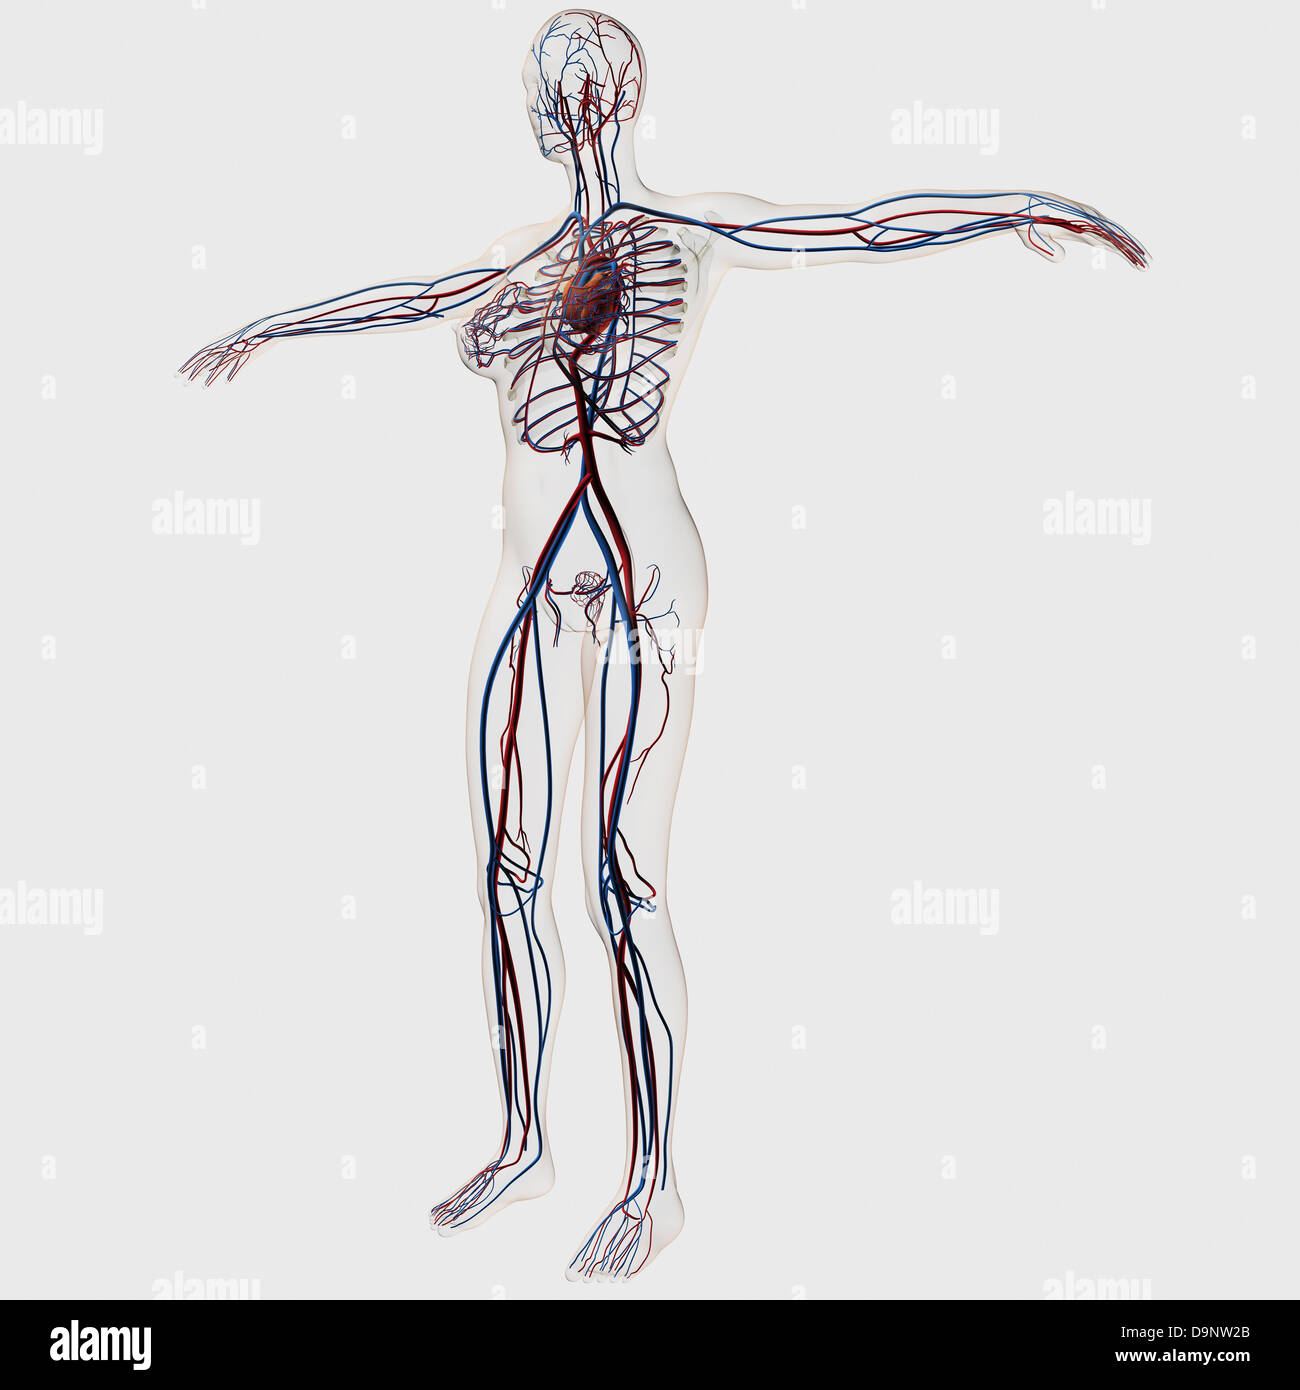

Medical illustration of female circulatory system with heart and veins visible, full body view. Stock Photohttps://www.alamy.com/image-license-details/?v=1https://www.alamy.com/stock-photo-medical-illustration-of-female-circulatory-system-with-heart-and-veins-57643666.html

Medical illustration of female circulatory system with heart and veins visible, full body view. Stock Photohttps://www.alamy.com/image-license-details/?v=1https://www.alamy.com/stock-photo-medical-illustration-of-female-circulatory-system-with-heart-and-veins-57643666.htmlRFD9NW2A–Medical illustration of female circulatory system with heart and veins visible, full body view.